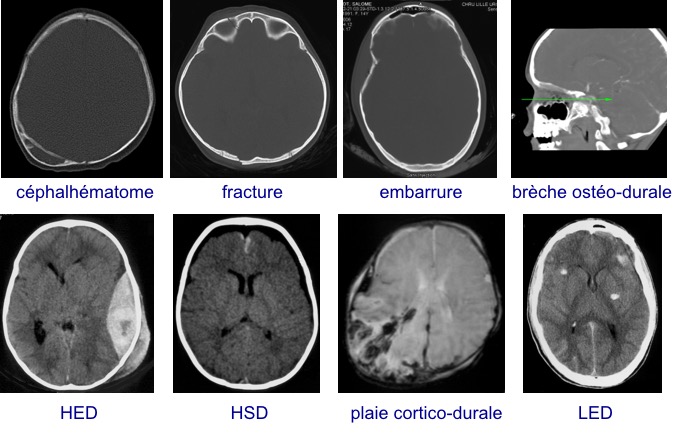

les différentes lésions traumatiques

certaines pathologies sont donc spécifiques :

d’autres sont très particulières chez l’enfant :

- le traumatisme crânien bénin

- la plaie du scalp

- l’embarrure

- l’hématome extra-dural

- la fracture de l’étage antérieur

- les autres plaies pénétrantes

- les lésions encéphaliques diffuses